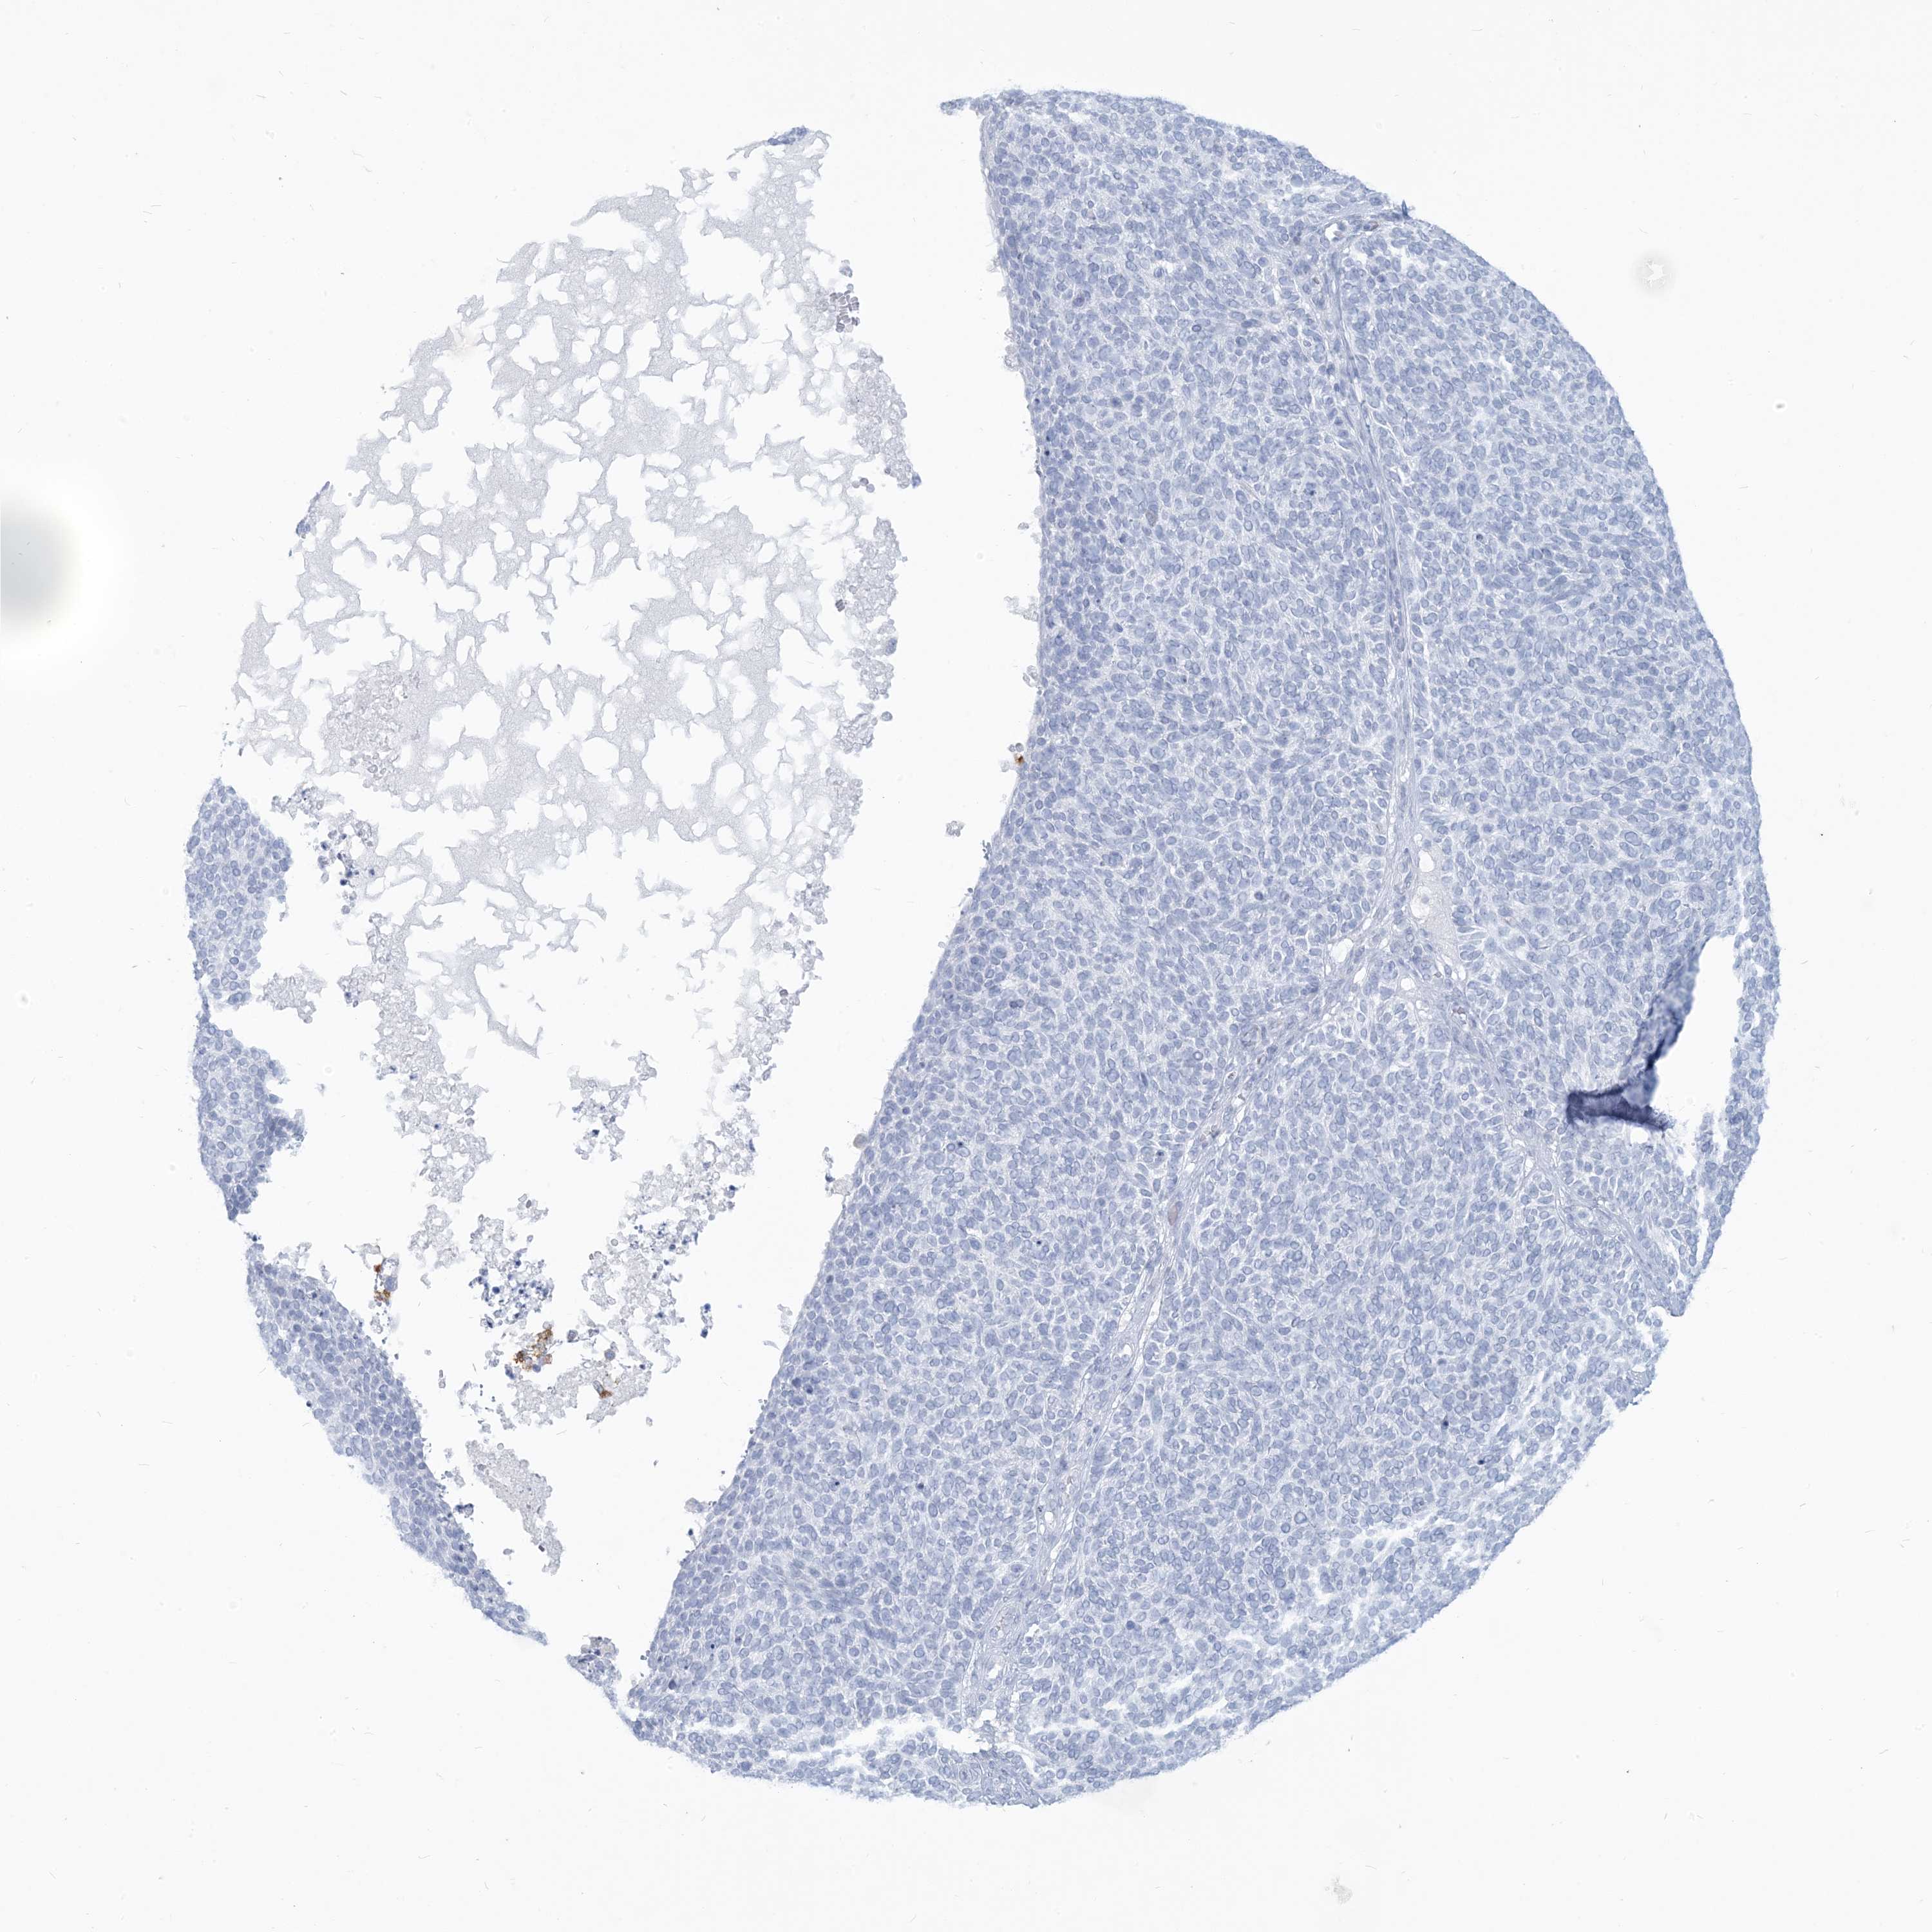

SKIN CANCER - Protein expressioni

A mouse-over function shows sample information and annotation data. Click on an image to view it in a full screen mode. Samples can be filtered based on level of antibody staining by selecting one or several of the following categories: high, medium, low and not detected. The assay and annotation is described here.

Antibody staining in the annotated cell types in the current human tissue is reported as not detected, low, medium, or high, based on conventional immunohistochemistry profiling in selected tissues. This score is based on the combination of the staining intensity and fraction of stained cells.

Each image is clickable and will lead to virtual microscopy that enables deeper exploration of all samples and also displays staining intensity scores, fraction scores and subcellular localization as well as patient and tissue information for each sample.

Antibody HPA043151

Basal cell carcinoma